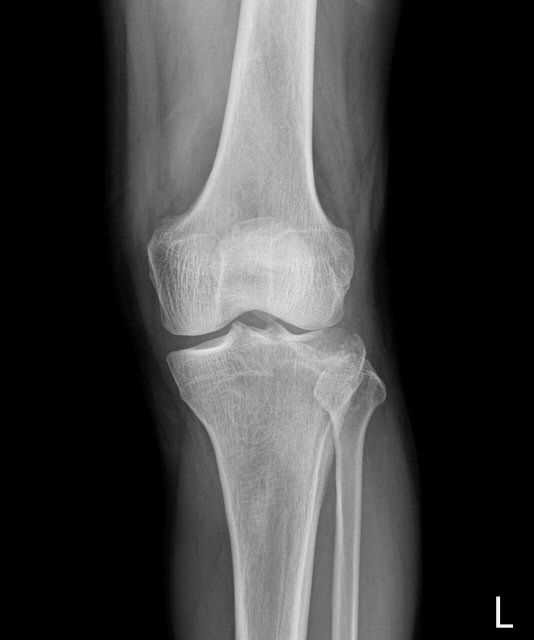

´Ü¼ø¹æ»ç¼±°Ë»ç

ƯÀÌ ¼Ò°ß ¾øÀ½, 1ÁÖ ÈÄ ÃßÀû°Ë»ç »çÁø¿¡¼­ ¹æ»ç¼±°¨¼âÀ½¿µÀ» º¸ÀÓ(»çÁø 6, 7)